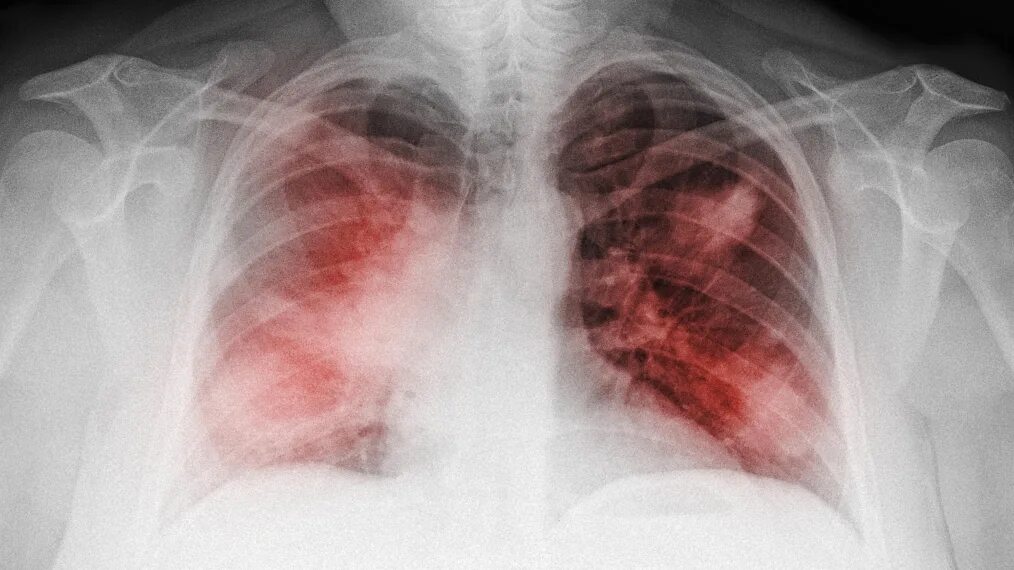

Как заболеть воспалением легких